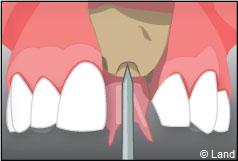

Le chirurgien-dentiste après une anesthésie locale pratique une incision, puis il décolle la gencive pour accéder à l’os alvéolaire.

Ensuite il prépare l’emplacement de l’implant dans l’os en passant plusieurs forets de diamètre croissant. Le forage de l’os se fait à vitesse maîtrisée et lente sous irrigation, pour respecter la structure osseuse et éviter tout échauffement de celle-ci. Le praticien arrête lorsqu’il a obtenu un puits d’un diamètre très légèrement inférieur à l’implant à poser.